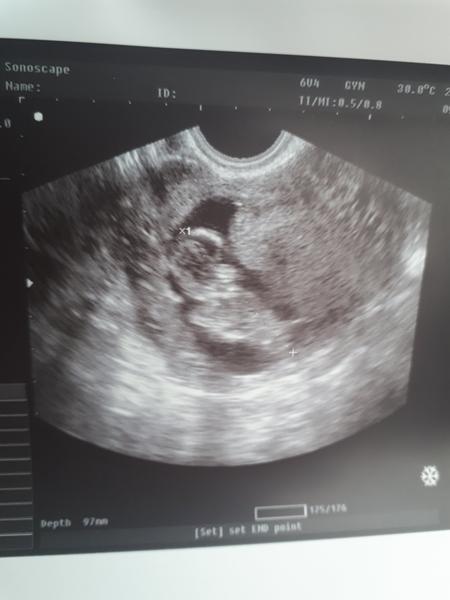

@simonkazga dopadli sme dobre. Drobec ma 5.5cm robil salta o dusu v brusku bolo to krasne. Len v moci som mala zvysene bielkoviny a ketony. Musim vela pit lebo moc tomu nedam.a toto je nas drobcek😘

@laydy7777 bambulka malicka 😍 nádherné správy 😘